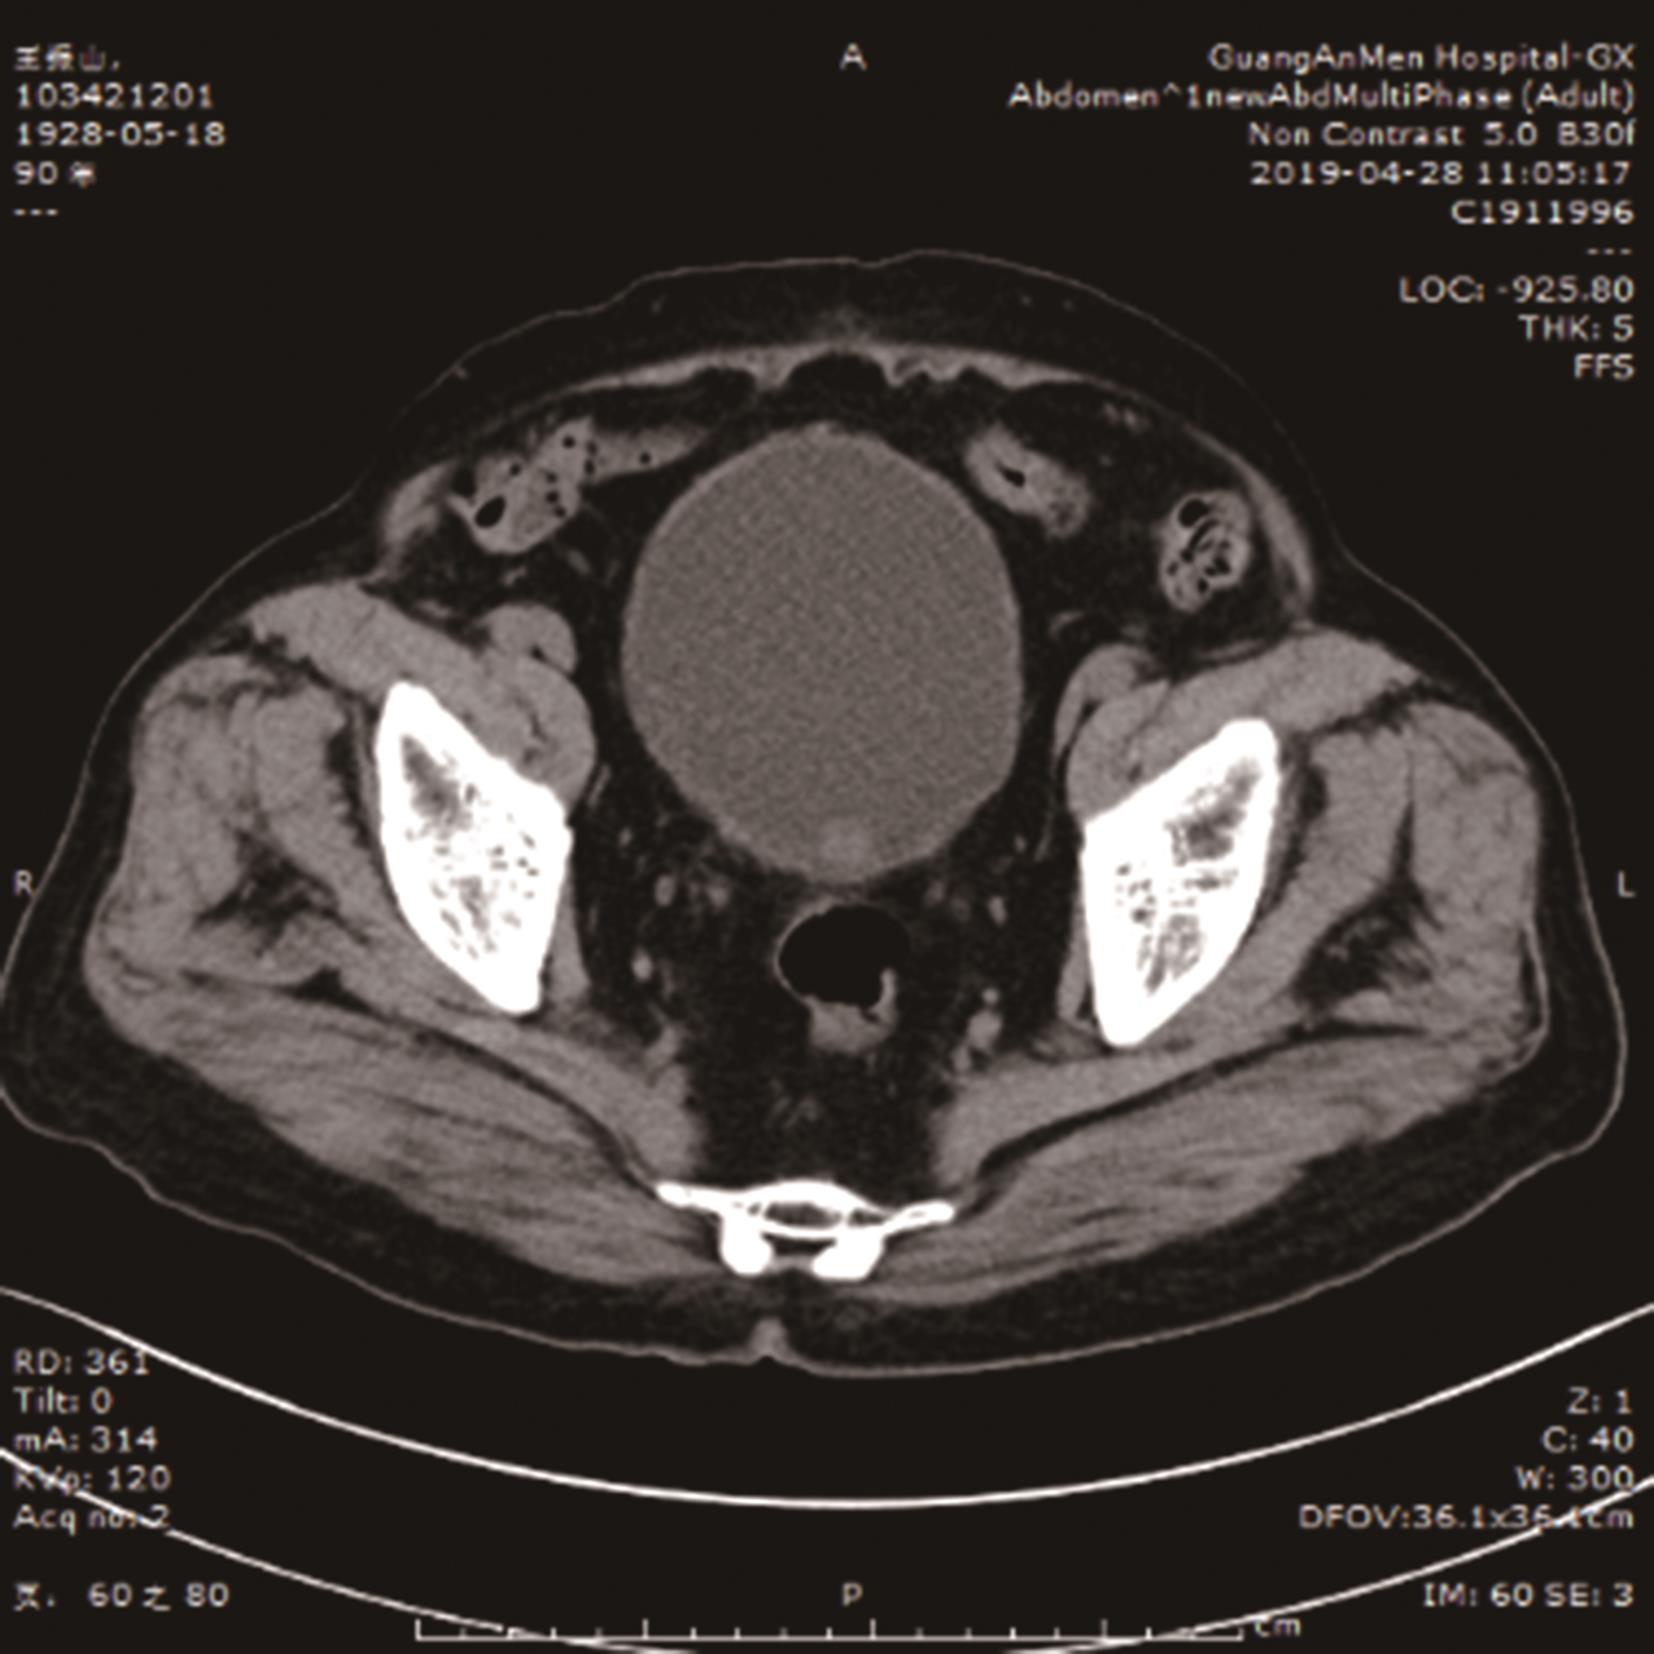

摘要:目的 探寻无法接受根治性手术治疗及放化疗的肌层浸润性膀胱癌病例的有效辅助治疗方式。方法 回顾性分析近10年广安门医院泌尿科肌层浸润性膀胱癌出院病例,统计患者治疗方式及保留膀胱时间。结果 61.90%应用膀胱肿瘤介入栓塞联合经尿道膀胱肿瘤切除术及中药治疗的患者达到了保留膀胱时间大于3年的治疗效果。结论 应用中西医结合治疗方式可能辅助延长肌层浸润性膀胱癌患者保留膀胱时间,改善患者预后及生存质量。